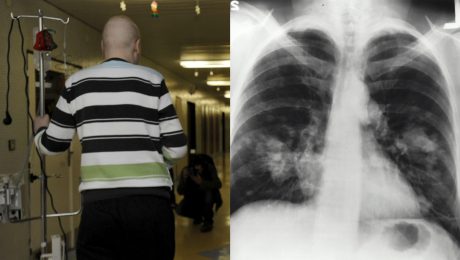

Na najrozšírenejšie druhy

Na najrozšírenejšie druhy rakoviny umrie na Slovensku cez 10 ľudí denne. Zisti, čo sú najväčšie hrozby